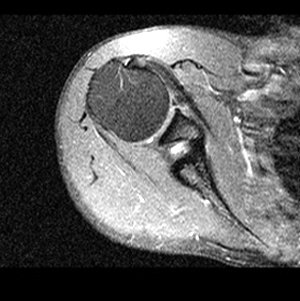

Bild 1: Schulter von oben.

In der nebenstehenden Kernspintomografie Aufnahme eines Schultergelenkes blicken wir von oben auf ein Schnittbild der Schulter und sehen dunkel auf der linken Seite den sehr grossen Oberarmkopf, der einer vergleichsweise kleinen Gelenkpfanne, rechts, gegenübersteht. Man kann sich kaum vorstellen, bei dem ungewöhnlich grossen Bewegungsumfang der Schulter, dass dieses Gelenk ausreichend stabil sein soll und nicht ständig zu Luxationen, zu Schulterausrenkungen führt. Erst eine mechanisch besonders wirkungsvolle Konstruktion von Muskelzügen und das geschickte Zusammenspiel von mehreren Gelenken ermöglicht die ausreichende Stabilität der Schulter.